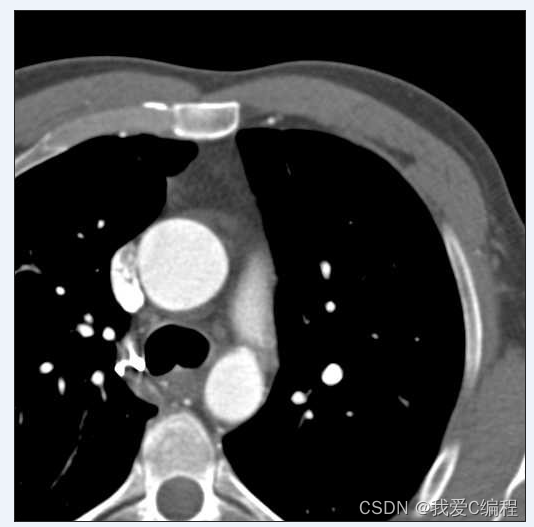

3.部分仿真截图